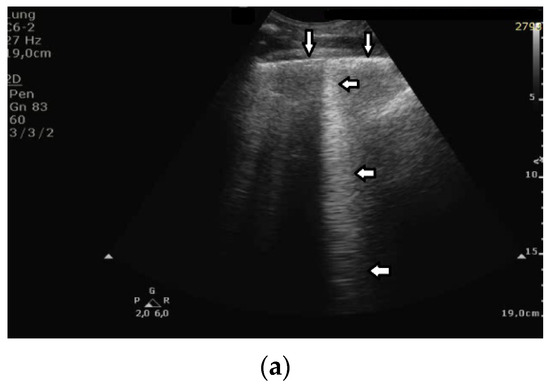

- Question 8:

Based on clinical observations, we know that in pulmonary fibrosis, B lines often reduce their length when higher frequencies are used on a convex probe (from 2 MHz up to 6 MHz) (see Figure 4a,b). In the case of cardiac edema, the length of a B line is often stable, irrespective of the frequency modification (see Figure 4c,d) [3]. Why does the length of B lines sometimes change when varying the pulse central frequency, whereas sometimes the length does not significantly change?

Figure 4.

(a) Pulmonary fibrosis in the course of interstitial lung disease: down arrows—pleural line; left arrows—B line artifact observed at 2 MHz frequency. (b) Pulmonary fibrosis in the course of interstitial lung disease: down arrows—pleural line; left arrows—vertical artifacts observed at 6 MHz frequency. The image was obtained from the same patient and identical assessment site as in Figure 4a. (c) Cardiac edema: down arrows—pleural line; left arrows—B-line artifacts observed at 2 MHz frequency. (d) Cardiac edema: down arrows—pleural line; left arrows—B-line artifacts observed at 6 MHz frequency. The image was obtained from the same patient and identical assessment site as in Figure 4c.

- Answer 8:

Look at the entire image, and you will find the answer. When using the 2 MHz frequency, the image (Figure 4a) is brighter everywhere: the thoracic wall is brighter; the pleura line is brighter; the two lateral sides of the image (where there are no artifacts) are brighter, and the artifacts themselves are brighter. In my opinion, the problem is primarily given by the attenuation, which increases when increasing the frequency. In order to compensate such an effect, you should change the TGC. As a rule of thumb, you can consider an attenuation coefficient of 1 db/cm/Mhz. When varying the frequency from 2 MHz to 6 MHz, you are introducing an additional attenuation of 4db per centimeter. From a practical point of view, when using the 6 MHz frequency, the probe receives a signal from the depth of half a centimeter, whose amplitude is less than half the amplitude of the signal it would receive from the same depth if a 2 MHz pulse were used. Moreover, it is worth noting that the ratio between the amplitudes of the two temporal signals s6(t) and s2(t) (the echoes received by the probe) decreases exponentially when the delay t increases.

The answer is a bit more complex when cardiac edema is considered. In the case of fibrosis, larger acoustic traps and wider linking channels are, in general, expected that reradiate almost the entire power spectrum of the trapped acoustic pulse. In this case, attenuation is probably the main factor that influences the artifact length when varying the frequency. Therefore, the artifact length decreases when increasing the pulse central frequency since attenuation increases when increasing the frequency. On the contrary, in the case of cardiac edema, smaller acoustic traps and narrower linking channels are expected at the early stages of the pathology. Smaller traps can reradiate only a few harmonics, and the overlapping between the pulse spectrum and the spectral signature of the trap affects the artifact length much more than the attenuation factor. In these cases, the trap response to pulses with different frequencies is unpredictable.